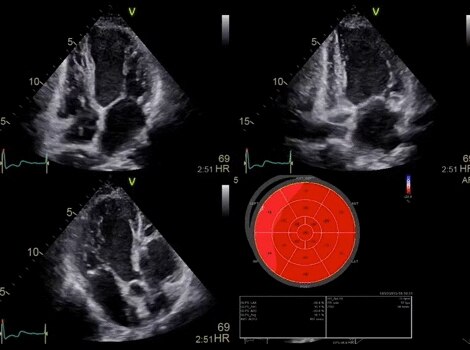

Vivid™ E95 4D Auto LAQ

Via a semi-automatic, surface-detecting algorithm, you gain fast, reproducible and accurate 4D quantification of the left atrium.  Read More

AFI Stress

Quantify wall motion at all stress levels. Integrated as part of a stress exam, AFI Stress protocols acquire standard apical 2D views and quantify both longitudinal segmental and global strain for contractility assessment at each stress level. Bulls-eyes from the different stress levels can then be easily compared. Read More